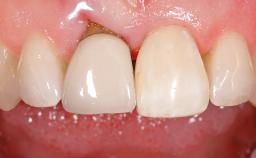

Treatment of Peri-Implant Mucositis at a Zirconia Implant

Frank Schwarz, Ausra Ramanauskaite

Recent clinical studies, most with short-to-medium term observation periods, have reported on the favorable clinical performance of zirconia implants in terms of survival rates, clinical, and radiographic outcomes (Roehling and coworkers 2016; Roehling and coworkers 2017; Rodriguez and coworkers 2018; Lorenz and coworkers 2019). Nonetheless, a rather high incidence of peri-implant disease at zirconia implants (39% of implants) was noted throughout a two-year period, highlighting the need for treatment protocols of peri-implant diseases at zirconia implants (Becker and coworkers 2017).